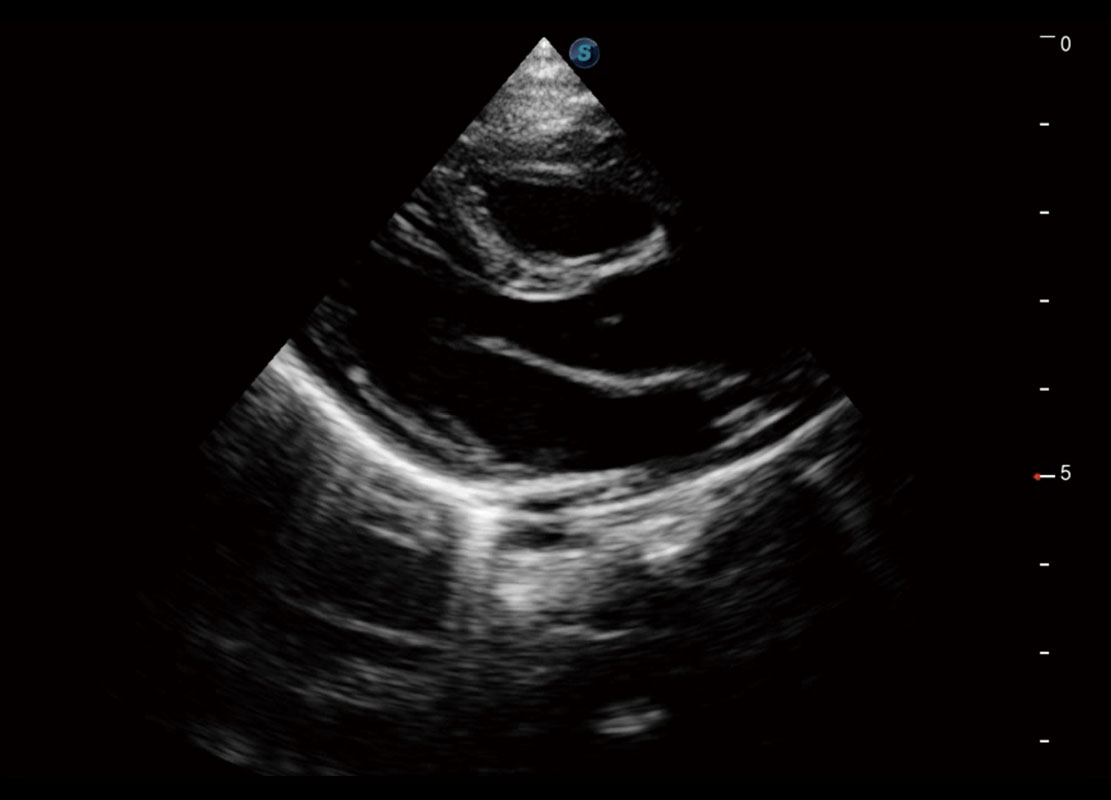

胎心筛查

P60搭载一系列胎儿心脏成像技术,实现精细的胎儿心脏评估。

• 四腔切面

• 四腔心血流

• 右室双出口

• 胎心容积成像

• 新生儿肝血管癌

• 新生儿心脏